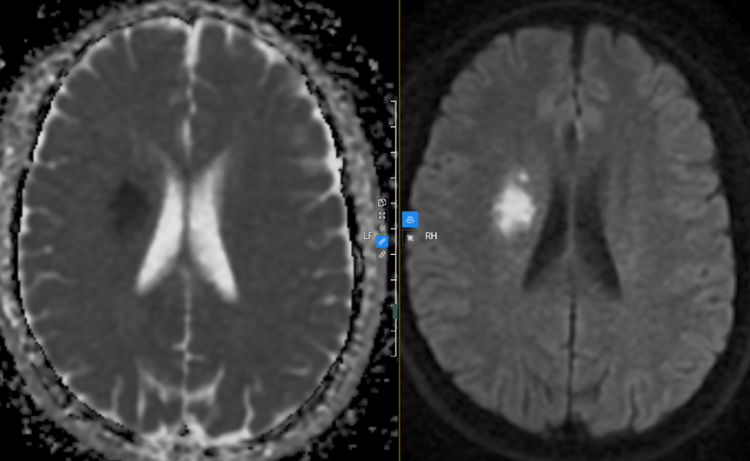

| Hình ảnh chụp MRI sọ não của bệnh nhân phát hiện bất thường. Ảnh BVCC |

Trên hình ảnh chụp MRI sọ não phát hiện ổ nhồi máu cấp tính vùng bao trong phải, giảm tín hiệu dòng chảy đoạn M2, M3 bên phải của động mạch não giữa. Bên cạnh đó, kết quả doppler động mạch cảnh cho thấy tình trạng dày lớp nội mạc động mạch dưới đòn phải và động mạch cảnh chung trái gây hẹp lòng mạch, mảng xơ vữa động mạch cảnh hai bên gây hẹp nhẹ lòng mạch.